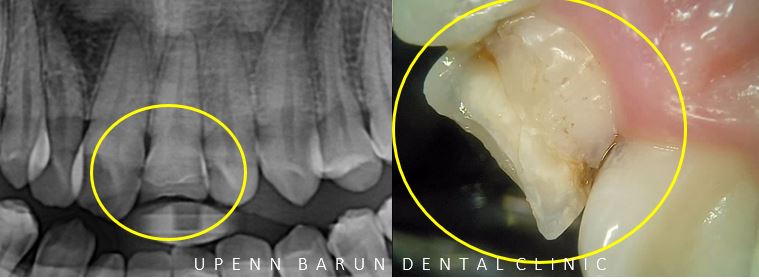

5년전에 떼웠던 부위 이기도 하고 범위가 워낙 커서

타치과에서는

'신경치료 후 씌워야 한다' 는 얘기를 듣고 오셨는데요 T^T

충치와 파절된 부위가 생각보다 커서

신경치료의 가능성이 높았지만

교정치료 전에

'신경치료를 하지 않고 ' 보존적으로 레진치료로 마무리 해드렸습니다.